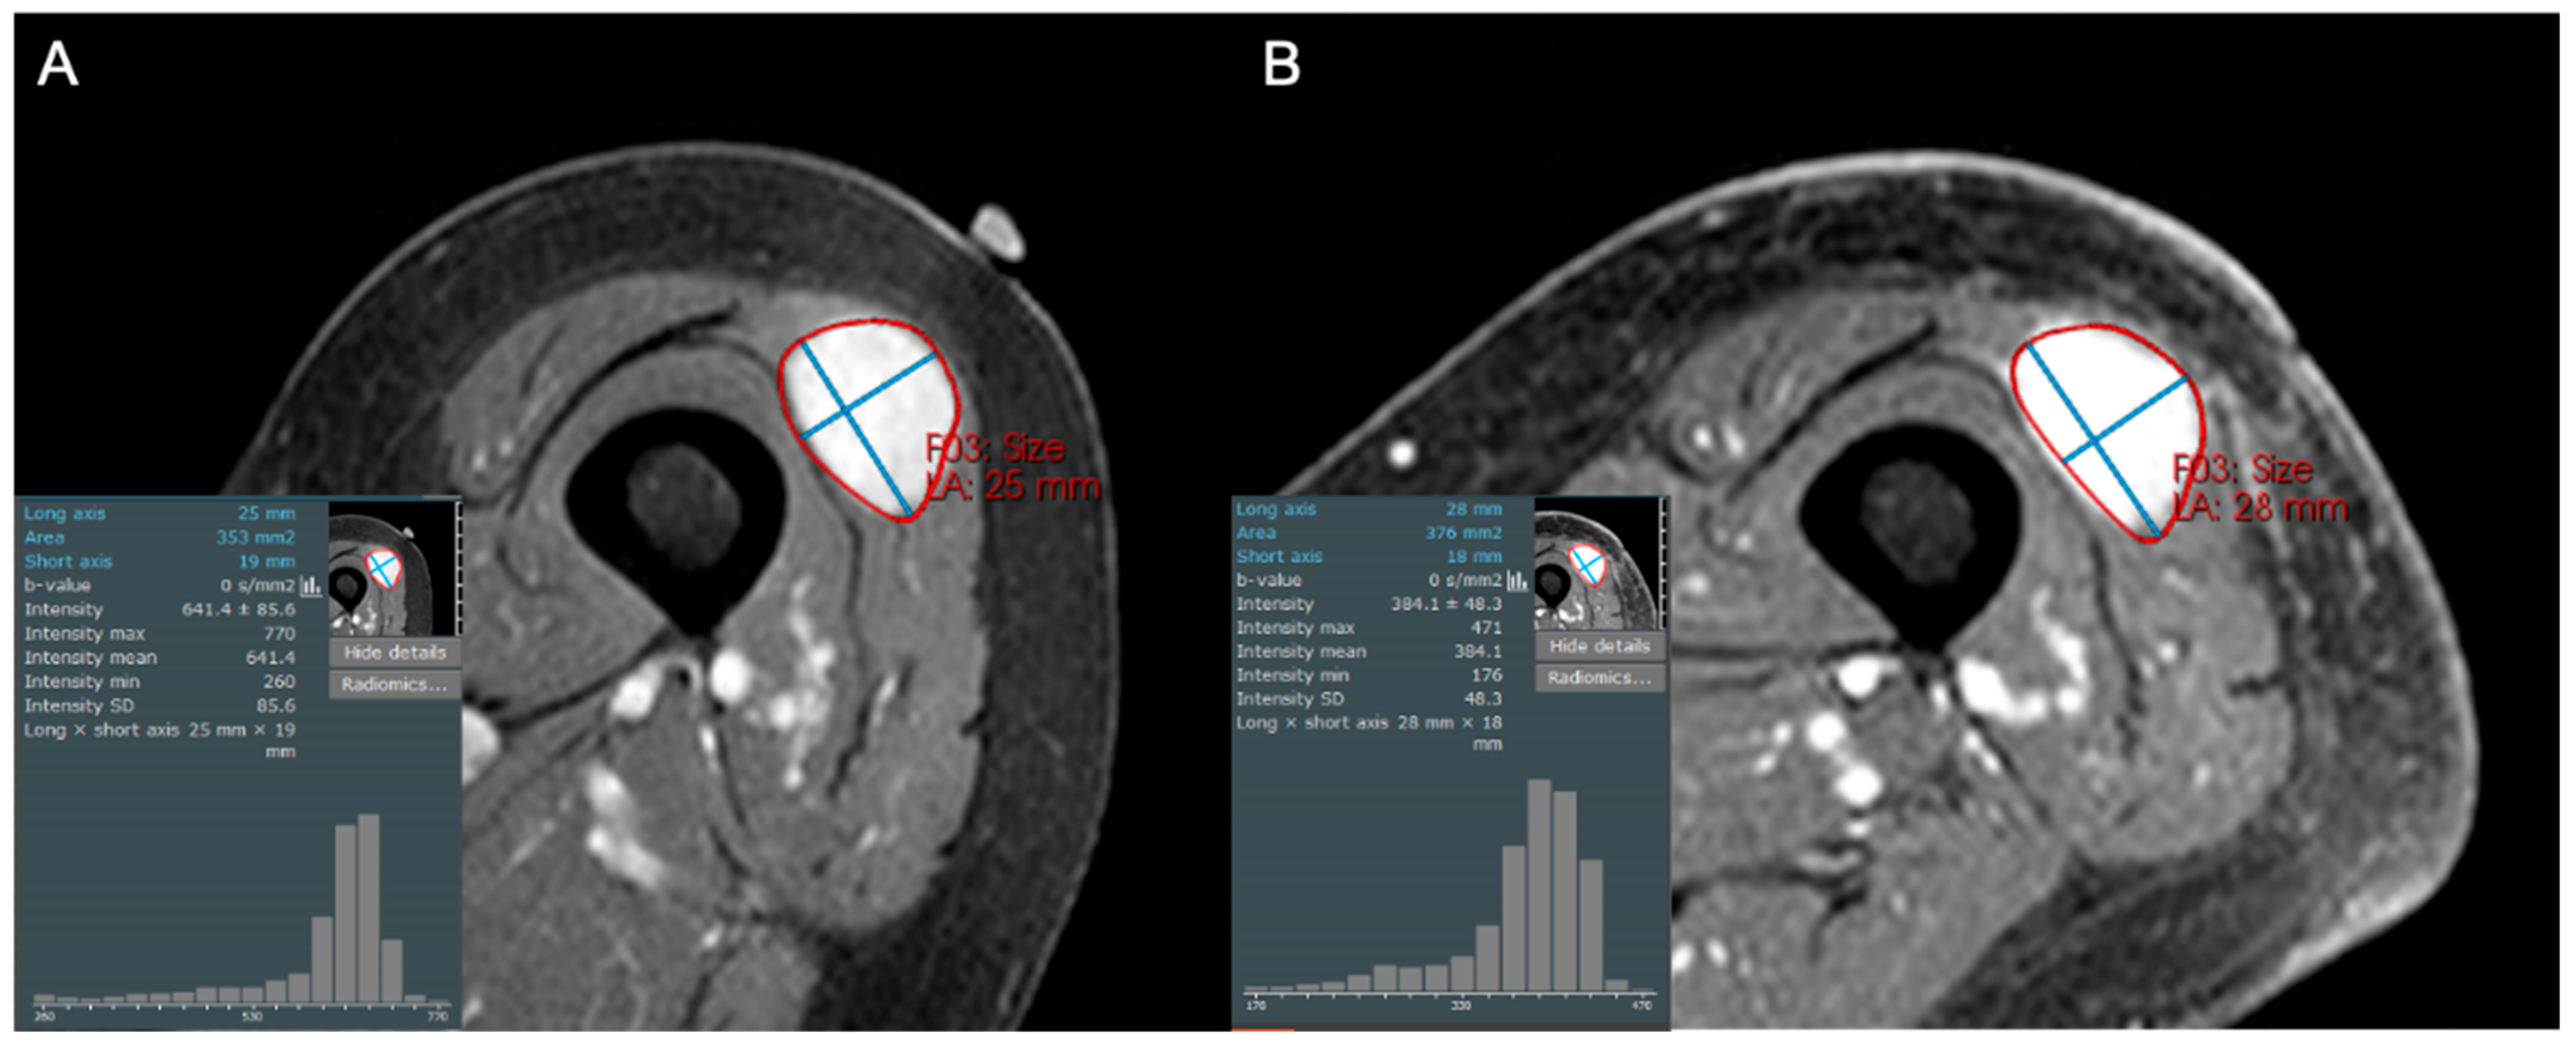

- Singer, A.D.; Pattany, P.M.; Fayad, L.M.; Tresley, J.; Subhawong, T.K. Volumetric segmentation of ADC maps and utility of standard deviation as measure of tumor heterogeneity in soft tissue tumors. Clin. Imaging 2016, 40, 386–391. [Google Scholar] [CrossRef]